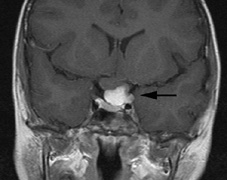

Although in Van der Hoeve's original description the term phakoma or phakomata was a generic term for the tumors occurring in various organ systems,1 it has become associated with the retinal astrocytic tumors of TSC,3 which occur in about 50% of affected patients and are bilateral in 25% to 30% (Table 3, Fig. 16).154,156

Fig. 16. Tuberous Sclerosis Complex: astrocytic retinal hamartoma, also referred to as retinal phakoma. There are three types: translucent type (a), calcified, nodular or “mulberry” type (b), and intermediate type (c).156 These usually do not affect vision and require no treatment. About half of patients are affected and there are bilateral lesions in 25% to 30%.154–156

Type 1. In the most common type, relatively flat, smooth-surfaced, and translucent lesions often difficult to see (an abnormal light reflex may be the only clue). They are in the posterior pole, superficial to the retinal vessels.156

Type 2. Raised, calcified, multinodular (“mulberry-like”) tumors in the posterior pole (80% within 2 disk diameters of the optic nerve).156

Type 3. The least common, intermediate type shows features of types 1 and 2, often in the posterior pole.156

Historically, the presence of mixed (type 3) hamartomas led to the suggestion of evolution from the type 1 to the type 2.157 A long-term photographic study found that although the types remained unchanged, a minority of types 1 and 3 increased in calcification and a new lesion was noted that had not been evident on an earlier photograph.157 All three types of retinal hamartomas may be found in young children. There is no correlation between age and the predominant type of lesion.156

Histologically, phakomata are composed of glial astrocytes—elongated, fibrous astrocytes with small oval nuclei, arising from the retina or the optic disc. The type 2 lesions contain basophilic, calcified drusen-like deposits within a dense vascular network. On fluorescein angiography, the type 2 lesions show autofluorescence, leakage with transit of dye, and marked late hyperflorescence.3,113

Astrocytic retinal hamartomas usually do not affect vision and require no treatment. Vitreous seeding and vitreous hemorrhage have been reported in association with phakomata, but these are rare.158,159 Laser photocoagulation may be considered in rare cases were exudation induces serous retinal detachments.160 The differential diagnosis of “white retinal lesions” includes retinoblastoma, toxoplasmosis and toxocara.3,113